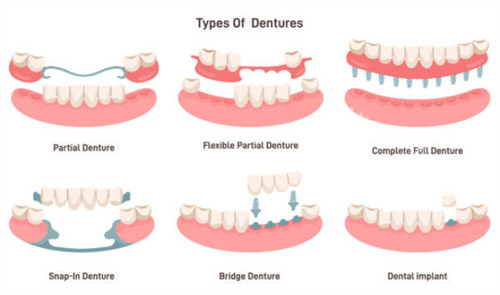

牙齿修复类项目

牙齿缺损或缺失的修复方案及价格: